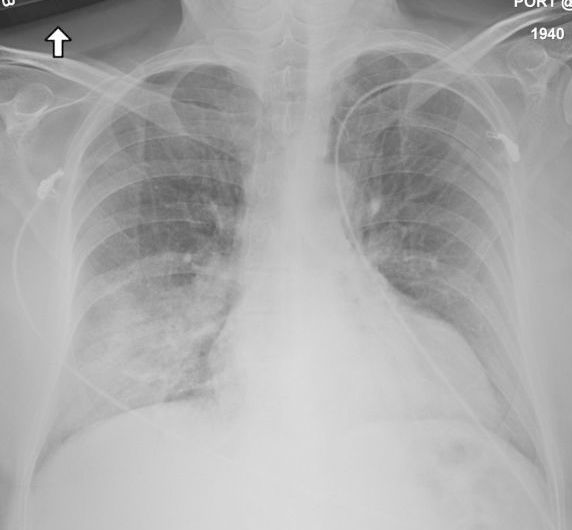

흉부 엑스레이에서는 바이러스성 폐렴 및 급성 호흡 부전 증후군(ARDS)과 일치하는 양측성 반점 침윤이 나타나는 경향이 있다. 아래쪽 폐엽이 더 많이 관여하는 경향이 있으며, CT 스캔에서는 간질 침윤을 확인할 수 있다.

5. 3. 영상의학

흉부 엑스레이 촬영에서는 바이러스성 폐렴 및 급성 호흡 부전 증후군(ARDS)과 일치하는 양측성 반점 침윤이 보이는 경향이 있다. 아래쪽 폐엽이 더 많이 관여하는 경향이 있다. CT 스캔에서는 간질 침윤이 관찰된다.5. 4. 검사실 검사